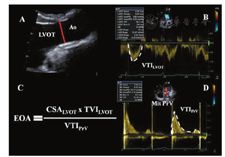

与跨瓣速度或压差相比,人工瓣膜EOA较少受血流的影响,因而是评价瓣膜内在血流动力学性能的更可靠指标(表1,表2)[19]。然而,这一参数更易出现技术性误差和测量误差。对人工主动脉瓣和人工二尖瓣来说,应该采用LVOT或偶尔右心室流出道(RVOT)测得的每搏量根据连续性方程法计算EOA(图7,图8)[106,111,112]。EOA反映的是跨人工瓣射流束(缩流束)的最小横截面积(CSA),计算公式:

EOA=CSA×VTILVOT/VTIPrV=0.785×(DLVOT)2×VTILVOT/VTIPrV

EOA = Stroke volume/VTIPrV

其中VTILVOT是指跨LVOT的血流速度时间积分,在LVOT内主动脉瓣(心尖切面)或偶尔肺动脉瓣(短轴切面)的近心端应用脉冲波(PW)多普勒测量获得;VTIPrV是应用连续波(CW)多普勒测量的跨人工瓣速度时间积分。很少用肺动脉瓣计算每搏量,但在LVOT无法评价时可以采用[19]。